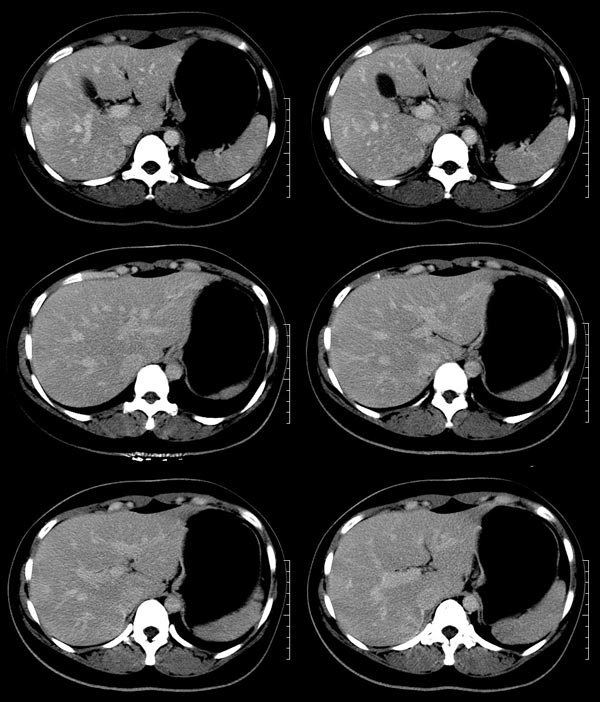

以下是引用52yingxiang在2007-9-16 10:16:00的发言:[br]肝脏局灶性结节增生影象表现(fnh)[br][br]肝脏局灶性结节增生是一种少见的肝脏良性肿瘤,可表现为边界清楚并无包膜的实质性肿块。病变大小不一,多系单发,亦可多发。组织学上是由结构紊乱的肝细胞、库普弗细胞、胆管、血管和粗厚的纤维性间隔所组成。[br]局灶性结节增生的ct表现可归纳为6点:[br]1、密度变化是其特征性改变,平扫多为低密度,少数为等密度,无论增强的早期或晚期均可能呈等密度,增强扫描有助于发现平扫为等密度的病灶;[br]2、中心疤痕,部分病灶在动态ct扫描时早期可看到中心疤痕增生性结节性病灶,ct血管造影也可看到普通ct不能显示的车轮状血管和车轴样改变;[br]3、纤维性分隔影,平扫为低密度,增强后为高密度;[br]4、包膜征象,增强后可以出现包膜强化,晚期较明显;[br]5、邻近血管的改变,主要是肝静脉受压,是发现等密度病变的重要依据;[br]6、瘤内胆管显影,这需要在胆管造影增强的情况下方能显示,出现率不高。[br][br]本例特点: 平扫低密度,增强动脉期明显强化,中心点条状低密度影(考虑纤维瘢痕),静脉期及延时期明显退减并与肝呈等密度,但中心仍可见低密度灶。[br]考虑肝脏局灶性结节增生(fnh)